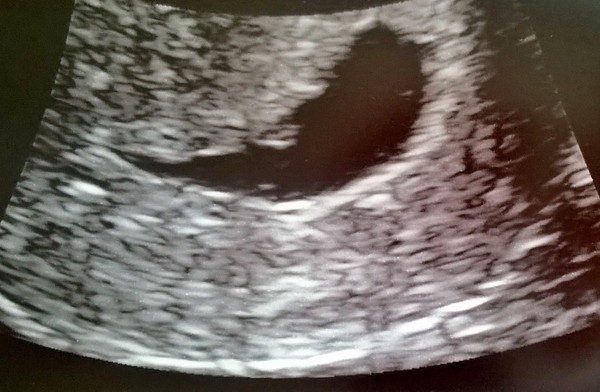

Thanks guys, I cried like a proper baby Blush dh said my head shot up instantly off the bed in epu when they said there's a hb! The sonographer told me off Wink

Congrats on 20 week scan bootles x